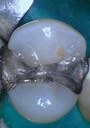

Joe Cha #20 amalgam removal